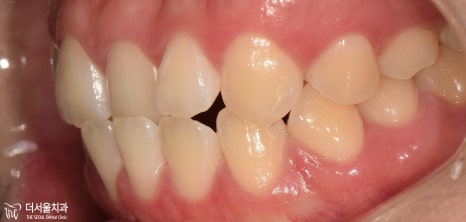

『인비절라인 기간 ’10개월’간의 기록 (초진)』

어?

아랫니가 윗니를 덮고 있는

‘반대교합(cross bite)’이 함께 나타나고 있군요.

정중선이 맞지 않는 것은 물론이며

전치부 치열에서 총생(crowding)도 함께 동반되었습니다.

이와 더불어,

전방으로 돌출되어 있는 모습이 관찰되네요.

과연 구치부의 상태는 어떨까요?